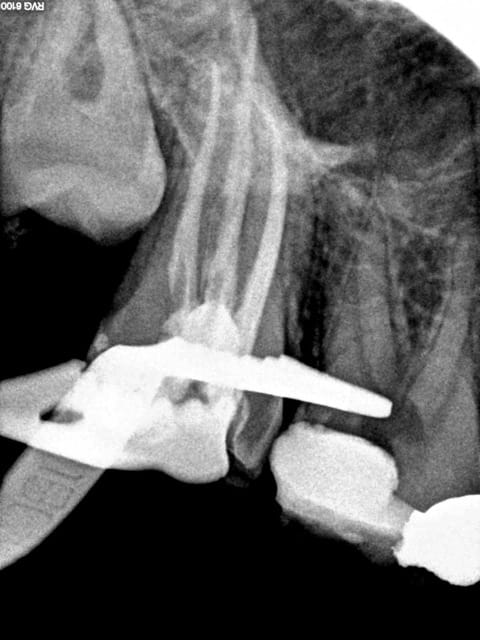

C'est sur. 1H pour 2 endos molaires c'est chaud, on finit par faire des conneries-))))

En espérant qu'ils soient en Y comme la 7.

R25 + digue ca fait gagner du temps. Ceci dit dans ce cas j'ai un peu grillé les étapes ( forcé) D'ou le faux canal sur le ml de 46.

Trop fort mon Chicot! Même la radio sépia, les photos et le faux canal sont beaux!

Une heure pour celle là , comme quoi, ca varie....